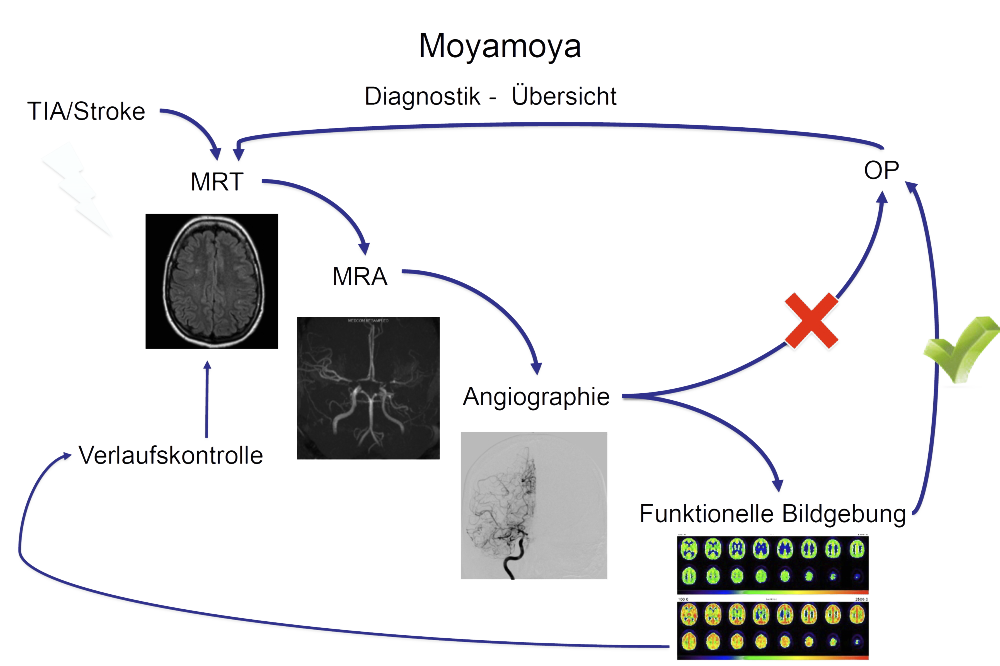

Um die richtigen Therapieentscheidungen treffen zu können, bedarf es einer ausführlichen diagnostischen Abklärung. Diese geht weit über die routinemäßig durchgeführten Untersuchungen hinaus und ist nur an einem Spezialzentrum mit ausreichend Expertise verfügbar. Durch unsere jahrelange klinische Erfahrung und Forschungsaktivitäten haben wir standardisierte diagnostische Abläufe für alle Patientinnen und Patienten definiert, um dann die therapeutische Strategie festzulegen.

So stellen wir sicher, dass nur die Patienten / Gefäßterritorien revaskularisiert werden (einen Bypass bekommen), die dies auch wirklich benötigen. Gleiches gilt auch für die Nachsorge nach operativer Bypassanlage, sowie alle Verlaufskontrollen bei konservativem Vorgehen ohne Bypassoperation.

In der MRT Bildgebung fertigen wir neben den Routine-Sequenzen der Schlaganfalldiagnostik spezielle hochauflösende Sequenzen auf einem modernen 3 Tesla Gerät an, die mit einer Auflösung von unter einem Millimeter die betroffenen Gefäßwände darstellen können. So kann eine mögliche Aktivität und ein Voranschreiten der Erkrankung erkannt und dementsprechend die weitere Behandlungs- und Kontrollstrategie angepasst werden. Im Rahmen unseres Forschungsschwerpunktes erforschen wir genau diese Veränderungen der Gefäßwände intensiv, um so das Voranschreiten der Erkrankung, sowie auch die Entstehung besser verstehen zu können.

Die konventionelle cerebrale Angiographie ist die wichtigste Untersuchung zur Diagnosestellung der Moyamoya Krankheit. Diese Untersuchung ist zu vergleichen mit einer Herzkatheteruntersuchung, eben nur mit Darstellung der Hirnarterien. Bei Moyamoya-Patientinnen und Patienten werden, im Gegensatz zu Routineuntersuchungen bei anderen cerebralen Erkrankungen, selektiv die vordere und hintere Zirkulation des Gehirns dargestellt, sowie auch die Versorgung der extrakranialen Gefäße. Diese umfassende Darstellung ist besonders wichtig, um die vollständige Ausdehnung der Erkrankung zu erfassen und alle möglicherweise veränderten Blutflüsse im Gehirn zu verstehen. Je nach Befund werden die Engstellen der Hirnarterien, sowie auch mögliche begleitende Veränderungen selektiv hochauflösend dreidimensional dargestellt. Es ist wichtig zu erwähnen, dass die Moyamoya Krankheit nicht über eine Katheterintervention (Ballonaufweitung der Engstelle) behandelt werden kann und darf. Dies haben mehrere Studien gezeigt.

In der konventionellen Angiographie und im konventionellen MRT können selektiv die Gefäße, der Blutfluss, und das Gewebe gut dargestellt werden. Diese Untersuchungen erbringen jedoch keine Aussage über den absoluten Blutfluss im Gehirn. Adaptierte Untersuchungen des MRTs, sowie auch des CTs zur Messung der Hirndurchblutung (Perfusion) haben sich in der Vergangenheit bei Moyamoya Betroffenen auf Grund der Kollateralen als zu wenig sensitiv gezeigt, um die Durchblutung zuverlässig darzustellen.

Durch die Erforschung und Weiterentwicklung des funktionellen MRTs haben wir eine Untersuchung etabliert, welche die Reaktivität der Hirngefäße (und somit indirekt die cerebrale Durchblutungsreserve) darstellen kann. Beim sogenannten "breathhold", also Atemanhalte-fMRT müssen die Patientinnen und Patienten in mehreren Zyklen für jeweils wenige Sekunden die Luft anhalten. Dadurch erhöht sich die CO2-Konzentration im Blut und die Hirngefäße stellen sich weiter. Diese Veränderung des Blutflusses kann dann indirekt gemessen werden. Da es sich hierbei um eine sehr neue Methode handelt, ist zu erwähnen, dass medizinische Entscheidungen primär ausschließlich in Zusammenschau aller Befunde und bei jeglicher Unschlüssigkeit mit dem ergänzenden PET/CT getroffen werden. Das fMRT hat sich jedoch als exzellentes Screening-Tool und für die langfristigen Nachkontrollen erwiesen.

Die wichtigste Untersuchung zur absoluten Darstellung des Blutflusses im Gehirn im Ruhezustand (baseline) und nach medikamentös stimulierter Gefäßweitstellung ("Diamox/Acetazolamid-Challenge") ist das sogenannte Wasser (H2 15O) PET/CT. Bei dieser Untersuchung wird eine definierte Menge kurzzeitig radioaktives Wasser in das Blutsystem appliziert und somit kann die absolute Blutmenge im Gehirn für jedes Gefäßterritorium bestimmt werden. Dies erfolgt dann sowohl im Ruhezustand und nach Medikamentengabe. Somit kann man die cerebrale Perfusionsreserve absolut darstellen und an Hand dessen Gefäßterritorien mit benötigter Revaskularisation (Anlage eines Bypasses) identifizieren. Auf Grund des benötigten speziellen Nuklearmedizinischen Setups kann diese Untersuchung nur an wenigen Orten in Deutschland durchgeführt werden. Hierfür kooperieren wir mit der Nuklearmedizin der Universität in Freiburg.